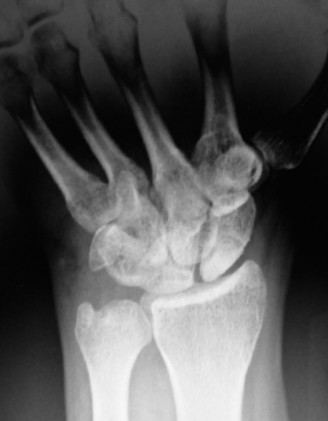

The same patient is seen in clinic 4 weeks later and still has persistent pain. An x-ray ordered at this time reveals the findings shown (Fig. 3–2). What is the more prudent thing to do next?

Figure 3–2(©) Sunil Thirkannad and Christine M. Kleinert.

The correct answer is (A). The x-ray reveals a fracture of the scaphoid. Healing rates are around 75% with nonsurgical treatment in adults compared to around 95% after surgery. However, since the patient is a 14-year-old child and has already been in a splint for 4 weeks, a prudent course would be to continue splinting for a further 2 to 4 weeks.